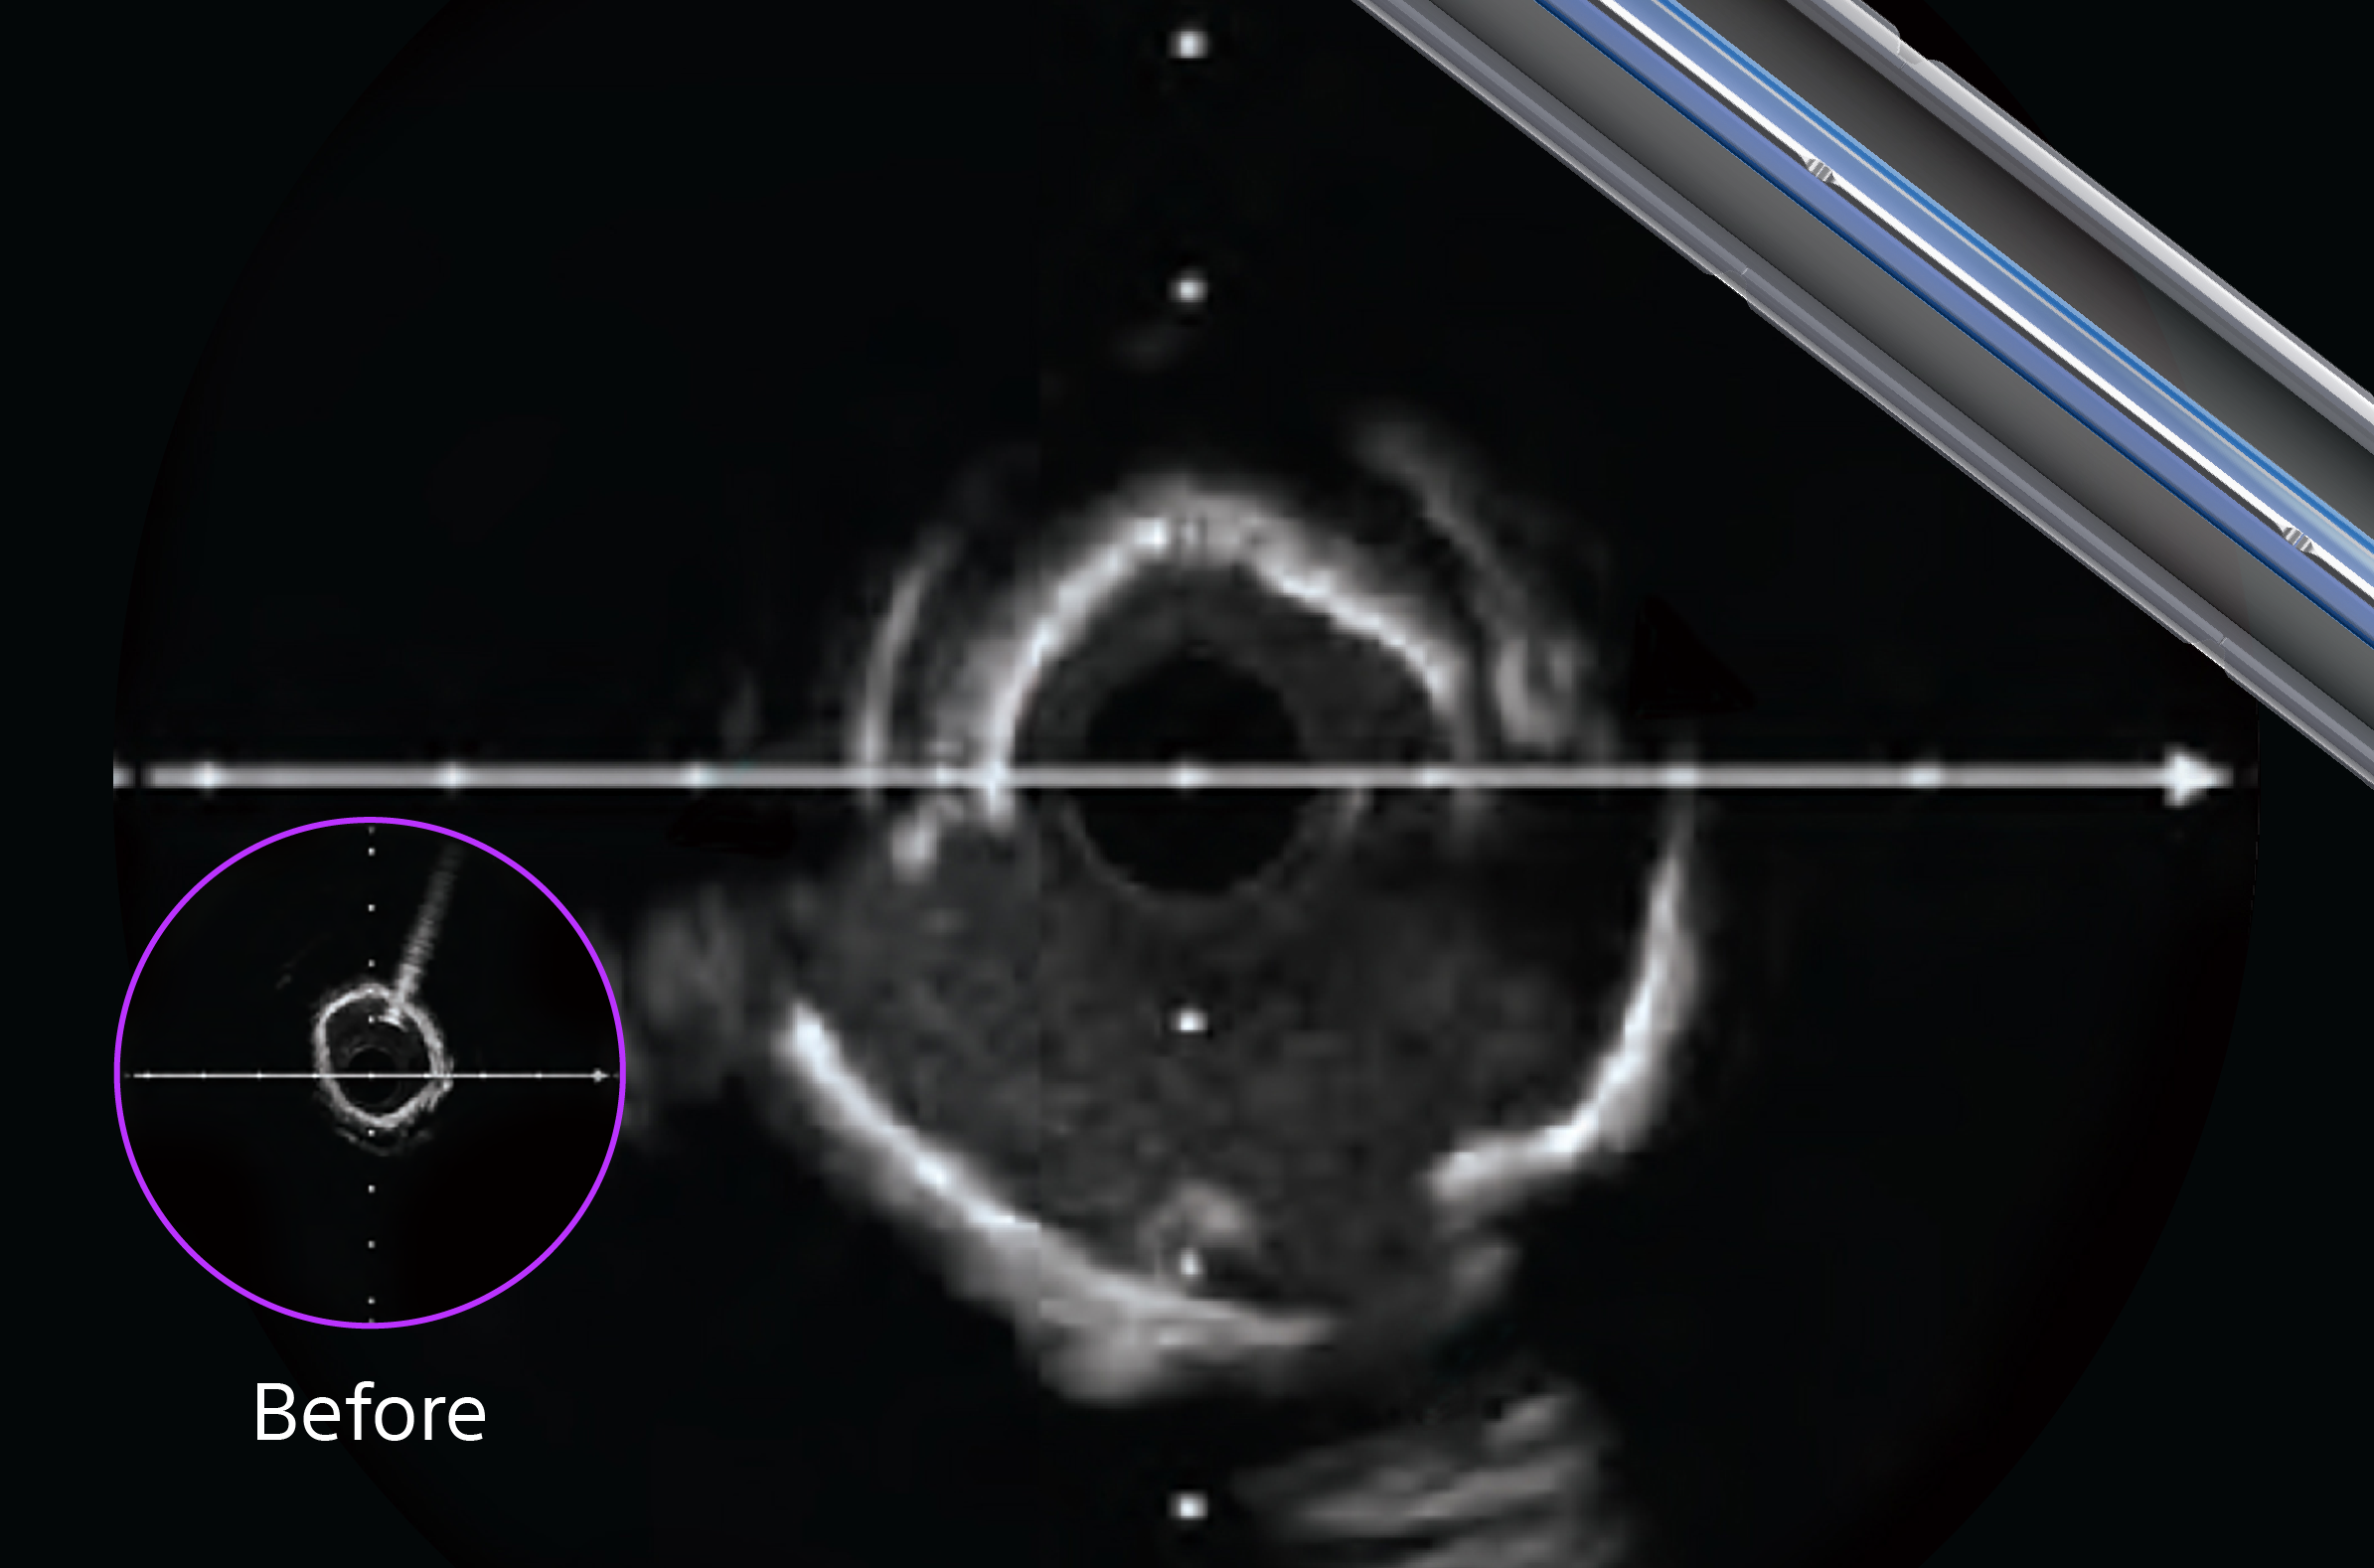

1. Neointimal modification: Has the neointimal tissue been adequately addressed? (Figure A)

2. Calcium modification: Is the calcium burden appropriately modified? (Figure B)

ISR lesion